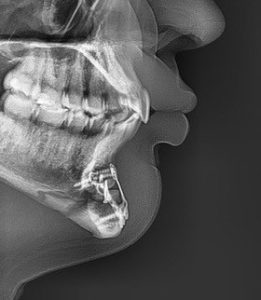

- 3D CT imaging is most informative x ray, lateral cephalometric and panorex at a minimum